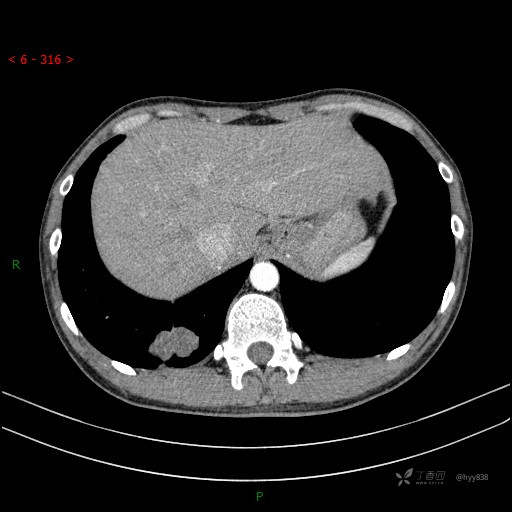

胸部CT平扫